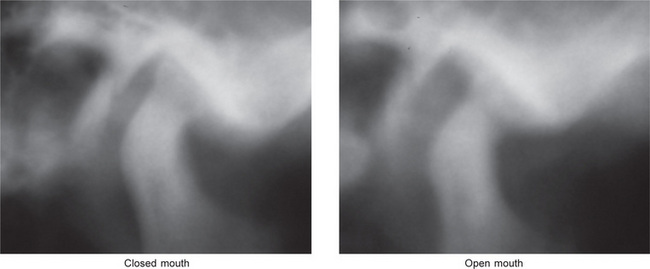

Figure 17-38 Ankylosis of the temporomandibular joint.

The images are tomography of the left temporomandibular joint in the closed and open mouth positions. A radiopaque band of tissues extends from the condylar head to the anterior slope of the articular fossa. On the open mouth view, the condylar head barely translated.